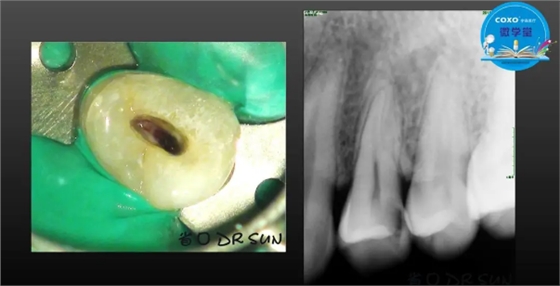

主讲:孙书昱

主任医师,牙体牙髓副主任, 广东省口腔医院牙体牙髓科 主任医师。2003年硕士研究生毕业,研究方向为牙体牙髓病学,擅长于牙体牙髓病的诊断、龋齿、牙髓炎、根尖周病的治疗以及前牙美容修复。